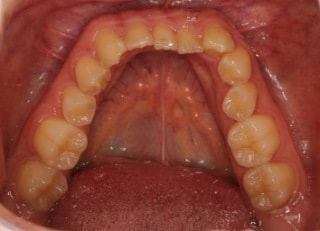

治療前